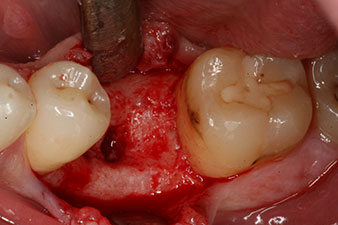

Abb. 2: Sechs Wochen später zeigt sich eine nur unvollständig ossifizierte Alveole im Bereich der mesialen Wurzel.

Sechs Wochen nach Extraktion zeigte sich jedoch nach Präparation des Mukoperiostlappens im Bereich der ehemaligen mesialen Alveole eine unvollständige Ossifikation.